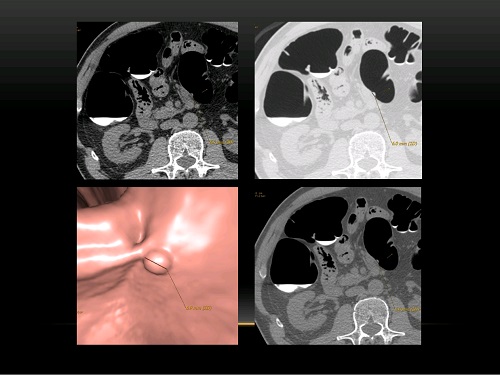

КТ кишечника: что показывает исследование?

Показания к виртуальной колоноскопии

Проведение виртуальной колоноскопии

Подготовка к КТ-колоноскопии

Расшифровка полученных данных